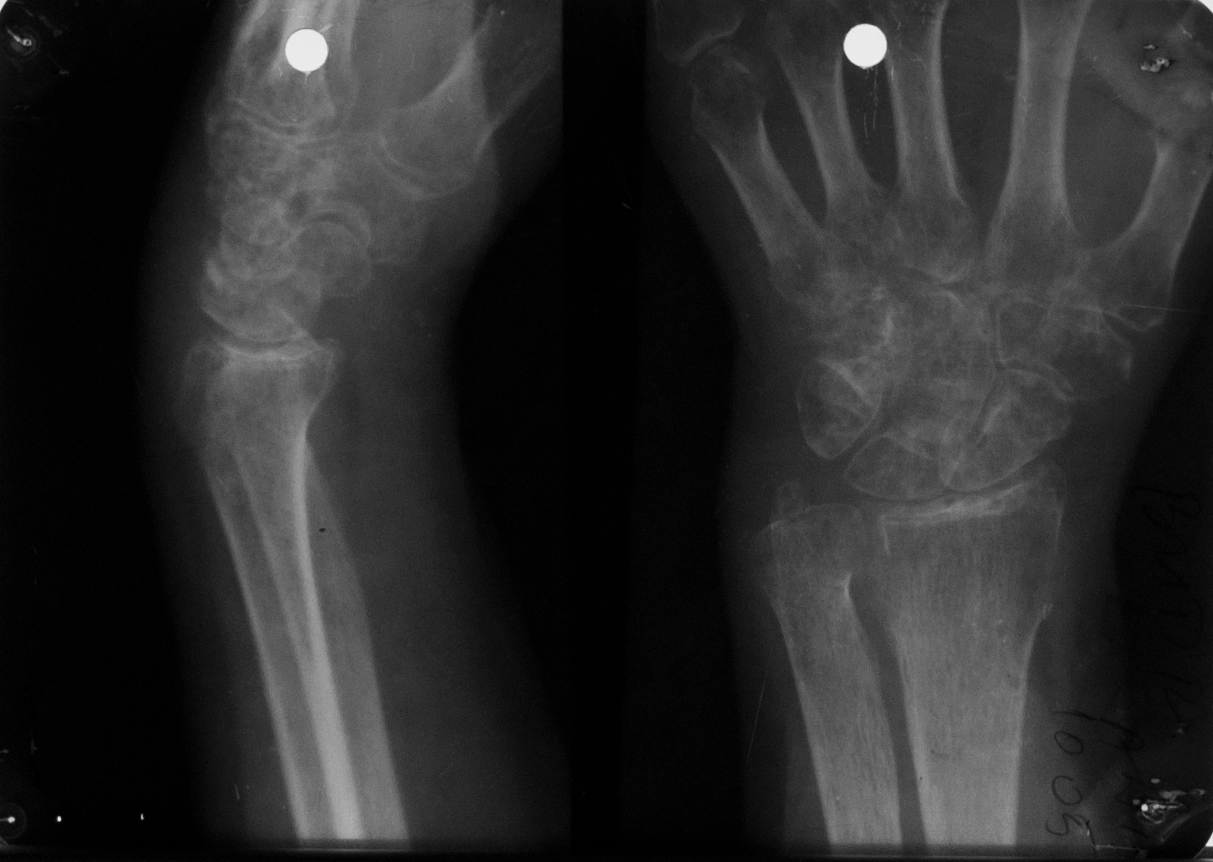

Osteoporoza in bandă, care e stadiul incipient (stadiul I) de poliartrită reumatoidă

Radiografie comparativa de maini, in care se vede o transparenta crescuta a extremitatilor metacarpienilor (adica a capetelor metacarpienilor, respectiv a bazelor falangelor)

Stadiul II spre III de poliartrita reumatoida

Radiografie comparativa de maini, cu osteoporoza accentuata, cu spatii disparute la nivelul oaselor carpiene si lize semnificative la nivelul spatiilor articulare interfalagiene proximale (deci bazele falangelor, respectiv capetele falangelor proximale), lize marginale cu disparitie de spatii articulare – stadiul 2 spre 3 de poliartrita reumatoida

MODIFICĂRI DE STADIUL 3 DE POLIARTRITĂ REUMATOIDĂ

Osteoporoză accentuată,absenta spațiilor articulare și distrucția severă ale oaselor carpiene,lize,osteolize și subluxații ale falangelor una pe cealaltă cu derivație pe cubitus(derivație cubitală)